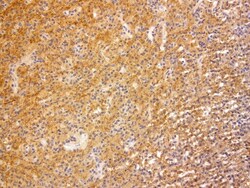

- Submitted by

- Invitrogen Antibodies (provider)

- Main image

- Experimental details

- Immunohistochemical staining of paraffin-embedded human glioma using anti-VSNL1 clone UMAB115 mouse monoclonal antibody (UM800034) at 1:200 with Polink2 Broad HRP DAB detection kit; heat-induced epitope retrieval with GBI Citrate pH6.0 HIER buffer using p